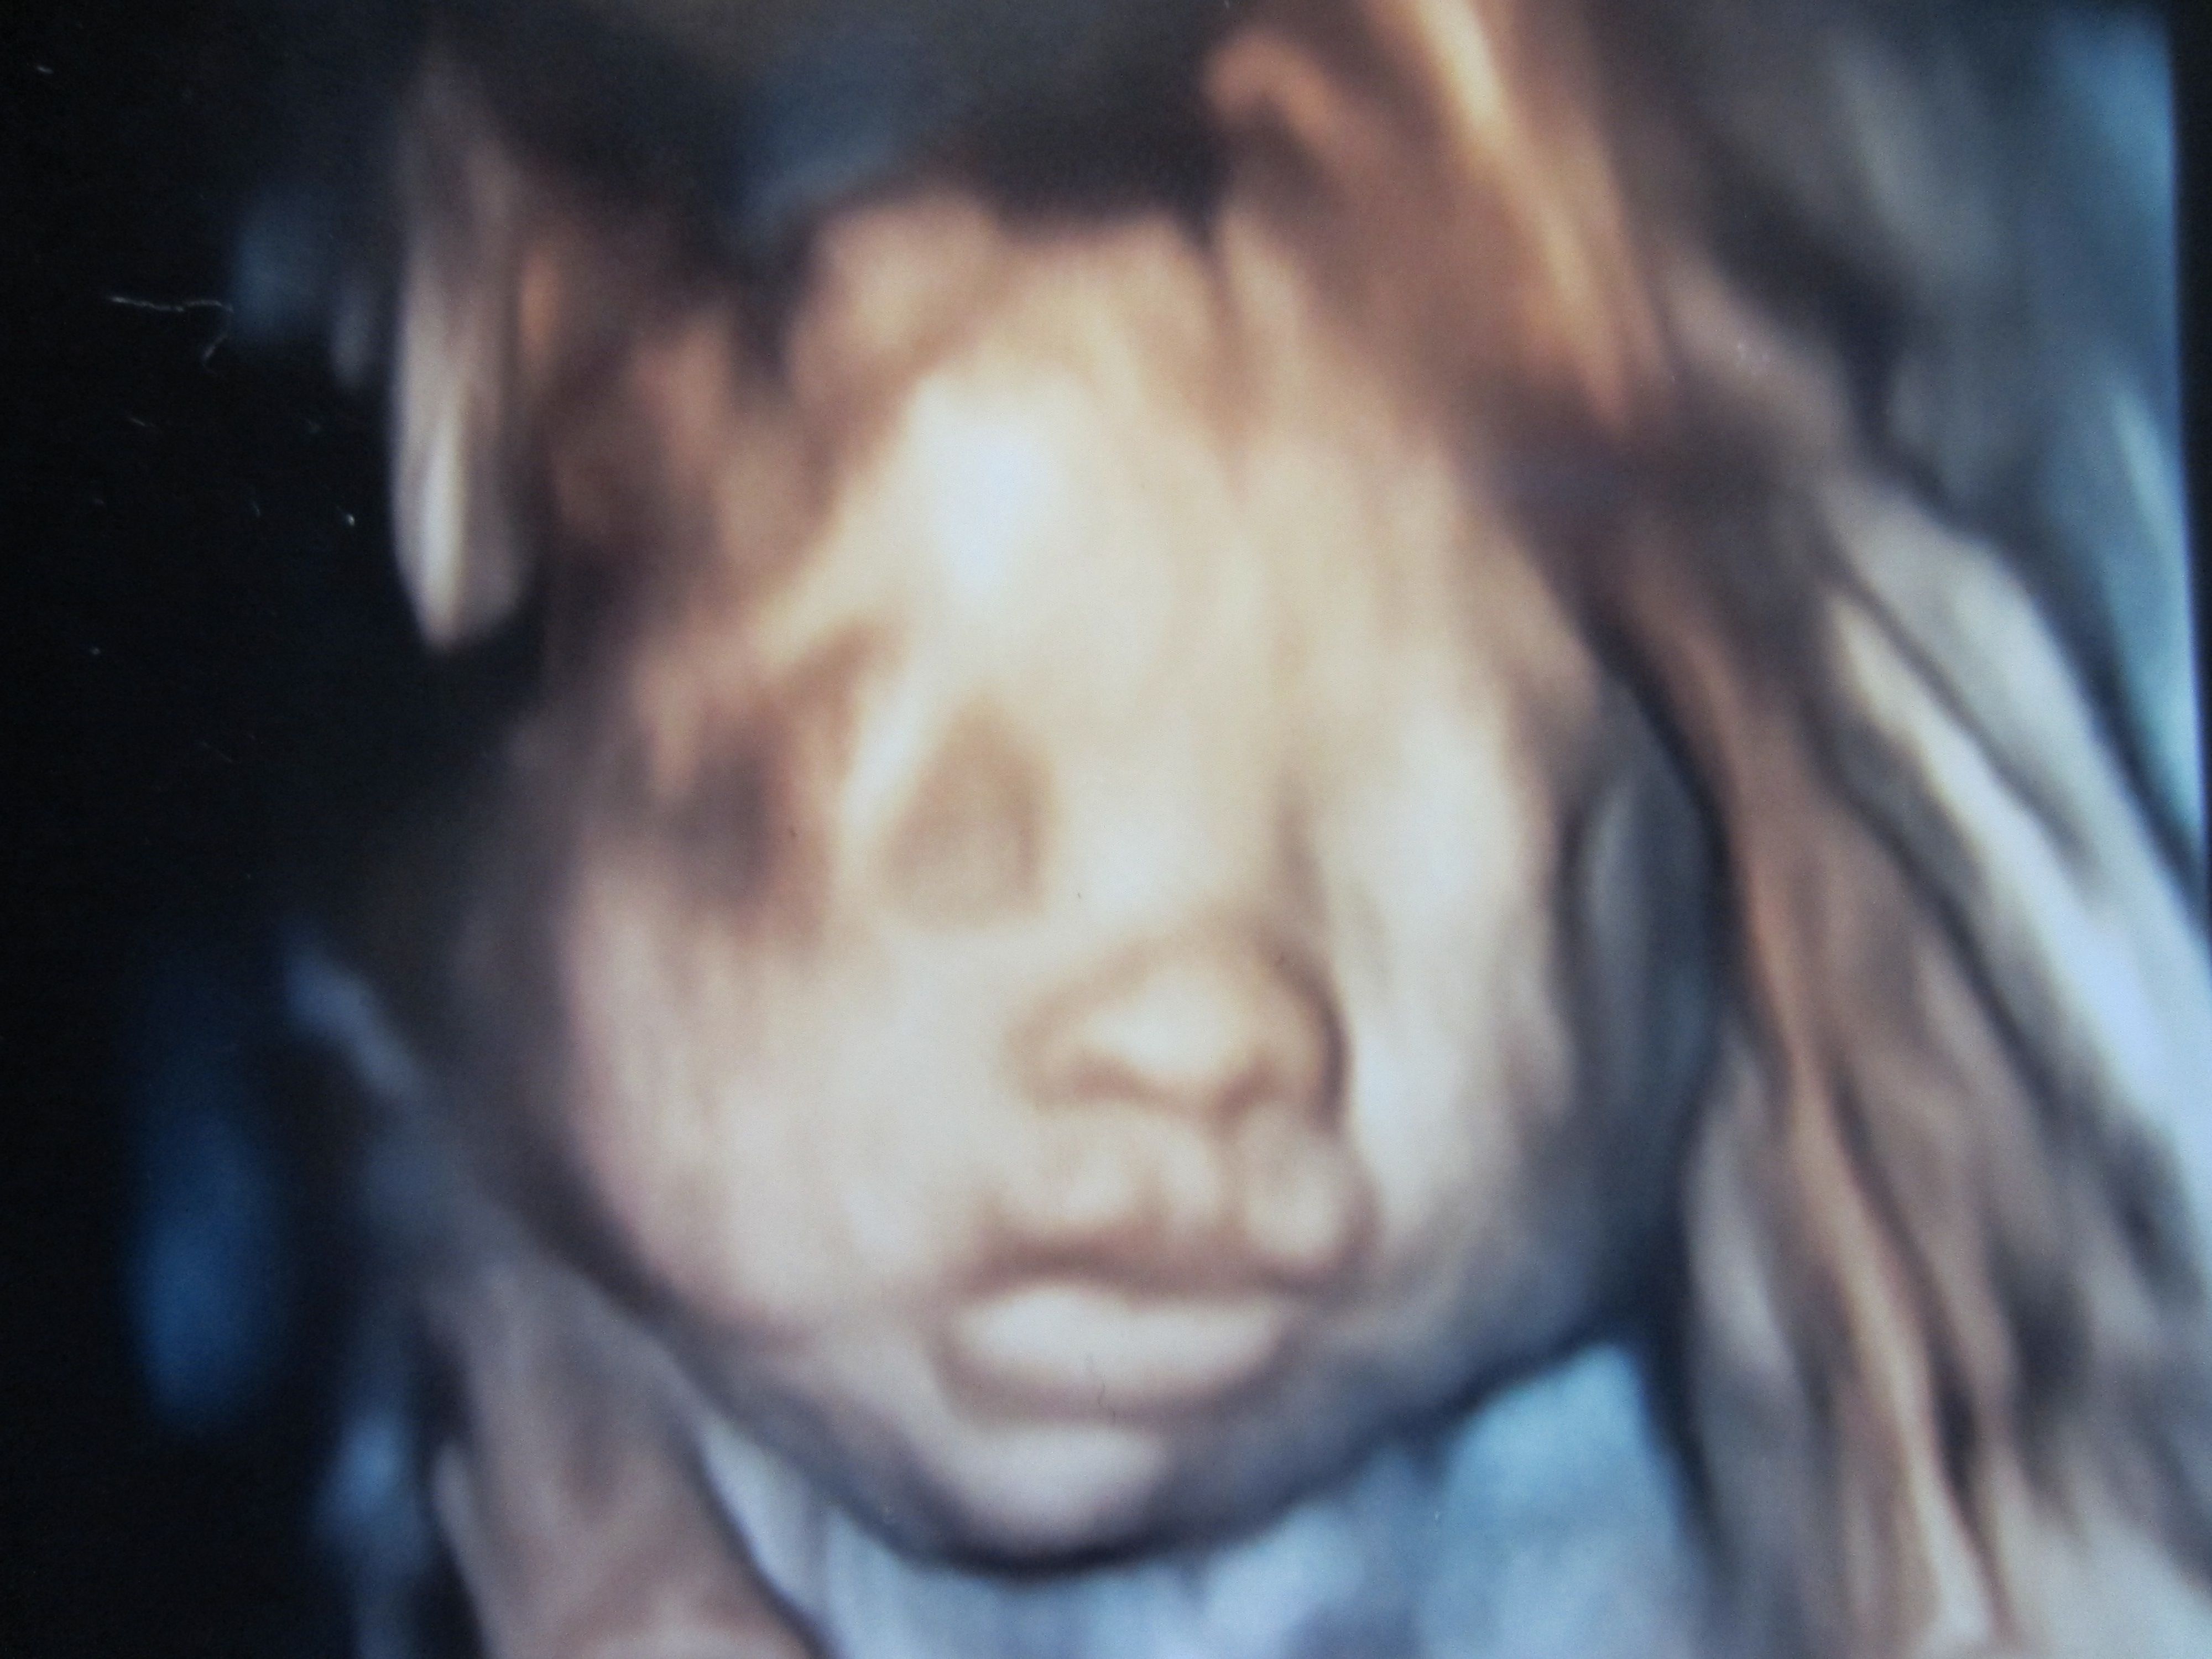

怀孕27周 照了四维彩超,总感觉孩子的嘴型怪怪的,上下嘴唇很厚 请问有病或问题吗?是女儿 点击展开 匿名用户 2013-11-06 16:32 为您推荐: 其他回答 病情分析: 你好,这种情况考虑属于常见的, 指导意见: 目前这个问题我建议顺其自然,基本没问题啊 白其雨_6xwx 2013-11-06 16:43 相关问题 怀孕27周做四维彩超,总觉得孩子的上嘴唇有点毛病,有专业的帮忙看一下 怀孕7周,嘴唇很干 怀孕18周 前段时间开始一直牙龈出血严重,前几天上嘴唇和下嘴唇长了一层东西,最近开始感觉很涩,牙龈